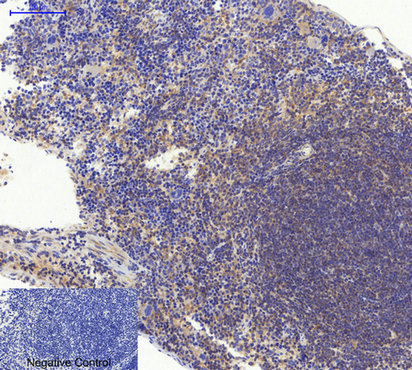

Immunohistochemical analysis of paraffin-embedded Mouse-spleen tissue. 1,Actin β Polyclonal Antibody was diluted at 1:200(4°C,overnight). 2, Sodium citrate pH 6.0 was used for antibody retrieval(>98°C,20min). 3,Secondary antibody was diluted at 1:200(room tempeRature, 30min). Negative control was used by secondary antibody only. |